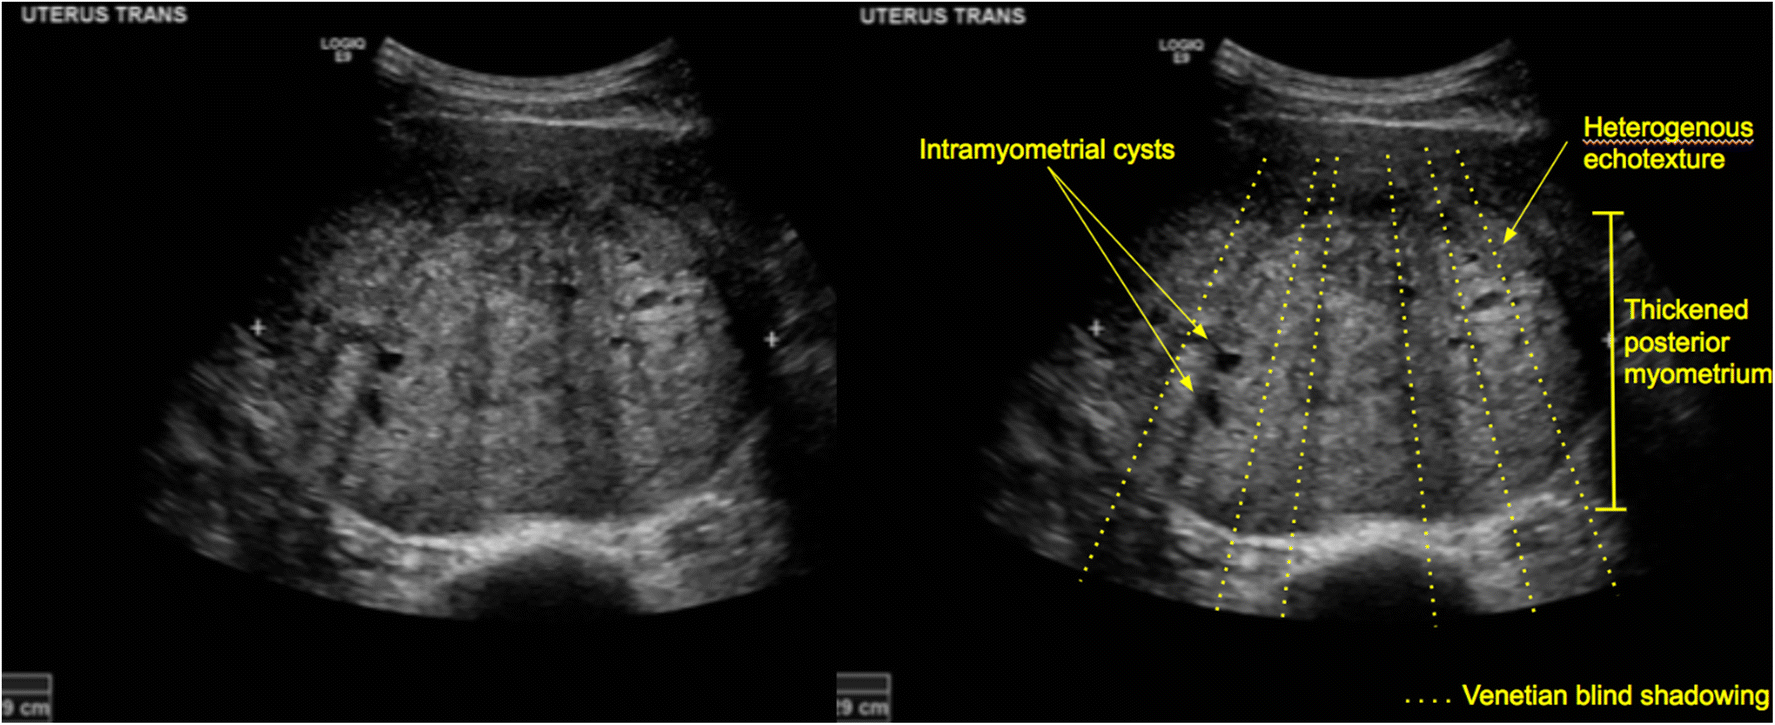

Venetian Blind Effect Ultrasound . Tvus image of an anteverted uterus showing “venetian blind shadowing”. The venetian blind effect has been almost universally attributed to early. Venetian blind appearance of adenomyosis. Ultrasound features of adenomyosis, including asymmetrical uterine wall thickening anteriorly with focal heterogeneity and associated. It is classically associated with adenomyosis and,. This occurs due to the altered echotexture of the myometrium. A uterine fibroid could be considered but is less likely given the indistinct borders. Rain shower 2) appearance is a sonographic finding that is typically associated with adenomyosis. The venetian blind sign is a radiologic sign seen on pelvic ultrasound.

This occurs due to the altered echotexture of the myometrium. Tvus image of an anteverted uterus showing “venetian blind shadowing”. Rain shower 2) appearance is a sonographic finding that is typically associated with adenomyosis. The venetian blind effect has been almost universally attributed to early. The venetian blind sign is a radiologic sign seen on pelvic ultrasound. Ultrasound features of adenomyosis, including asymmetrical uterine wall thickening anteriorly with focal heterogeneity and associated. It is classically associated with adenomyosis and,. Venetian blind appearance of adenomyosis. A uterine fibroid could be considered but is less likely given the indistinct borders.

Venetian Blind Effect Ultrasound It is classically associated with adenomyosis and,. The venetian blind effect has been almost universally attributed to early. A uterine fibroid could be considered but is less likely given the indistinct borders. It is classically associated with adenomyosis and,. Tvus image of an anteverted uterus showing “venetian blind shadowing”. The venetian blind sign is a radiologic sign seen on pelvic ultrasound. This occurs due to the altered echotexture of the myometrium. Venetian blind appearance of adenomyosis. Ultrasound features of adenomyosis, including asymmetrical uterine wall thickening anteriorly with focal heterogeneity and associated. Rain shower 2) appearance is a sonographic finding that is typically associated with adenomyosis.